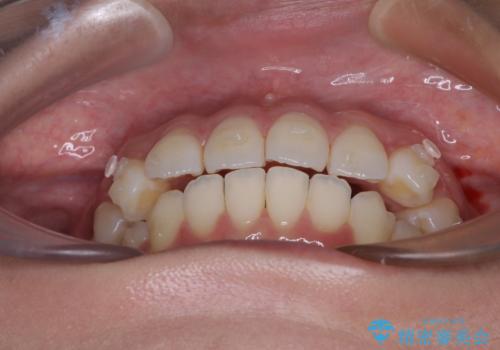

前歯のデコボコを解消 インビザラインの矯正治療

- 前歯のデコボコを治したいとのことで来院された患者様です。

上下顎ともに歯列全体の後方移動とIPR(歯と歯の間を削る)によってデコボコが解消するように設計し、インビザラインにより治療を行うこととしました。

上下ともにIPRを積極的に行っているため、舌の突出癖をしっかりと改善できないと、後戻りにより隙間やデコボコが早い段階で発現することになるため、舌のトレーニングが非常に大切になります。